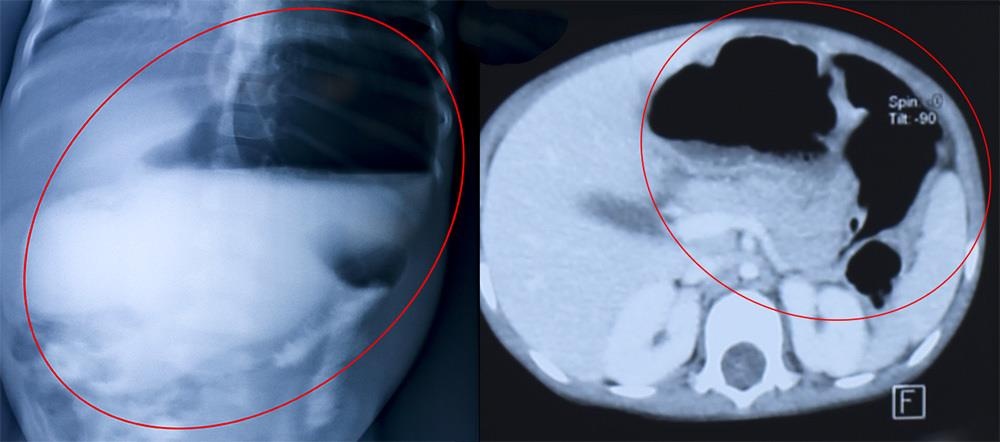

| Hình chụp X- quang dạ dày giãn lớn (trái) và hình MSCT dạ dày giãn lớn chứa nhiều thức ăn và gấp khúc. Ảnh: Vietnamnet. |

Qua thăm khám, chụp X-quang ổ bụng không chuẩn bị có hình ảnh bóng hơi kép, chụp lưu thông ruột kết quả dạ dày giãn to đến đoạn DII tá tràng, thuốc vẫn xuống tận đại tràng.

Chụp MSCT 128 dãy phát hiện dạ dày bệnh nhi giãn to có chứa nhiều thức ăn mặn dù đã cho bé nhịn ăn từ chiều hôm trước. Với kết quả khám lâm sàng và cận lâm sàng, bé P. được chẩn đoán tắc tá tràng không hoàn toàn do màng ngăn niêm mạc.